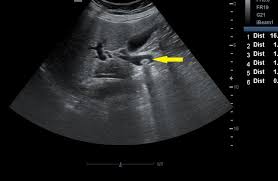

Bone Scans

Advantages of Bone scans over Conventional Imaging:

Early detection of bone metabolism changes, whole body screening

3 Phase Bone Scan: blood flow, blood pool, delayed.

Used for: osteomyelitis, prosthesis infection

SPECT/CT Benefits

SPECT: a nuclear medicine imaging technique that creates detailed, 3D images of organs, tissues, and bones by detecting the gamma rays emitted by radioactive tracers injected into the body

Benefits:

Combines function and structure so improved localisation

Superscan

Intense skeletal uptake with reduced renal/ST activity (eg: metastatic disease)

Common Indications:

? bony mets

Infection

Trauma

Arthritis